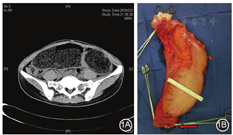

成人先天性巨结肠是由于远端结肠、直肠黏膜下神经丛和肌间神经丛缺乏神经节细胞所致[1]。其分型众多,大部分患者年幼发病,在幼儿或儿童时期已经得到外科干预,仅部分短段型和超短段型幼儿期症状轻微未得到及时处理,拖延至青年时期发病或就医,导致就诊时病变肠段近端的正常肠段高度扩张、肌层代偿性增厚形成橡皮样的肠壁;典型先天巨结肠影像见图1A。内科治疗成人先天性巨结肠效果差,外科手术是治疗该疾病的唯一方法,主要的手术方式有Swenson、Duhamel、Soave、金陵术、低位前切除术等。对幼儿时期发病者,宜选用Swenson、Duhamel、Soave术。2018年的报道显示,选用经肛直肠内镜下肌切开术(per-rectal endoscopic myotomy,PREM)可以取得良好的疗效[2]。该手术创伤小,有较好的使用前景,但是需要更多循证医学证据的支持。成人巨结肠者可以选用改良Duhamel、金陵术、低位前切除术或者拖出式低位前切除术,而腹腔镜手术的普及大大减小了手术创伤。结合临床经验,笔者认为,成年巨结肠的外科治疗不应拘泥于一种或者几种手术方式,只要遵循手术的基本原则,切除狭窄段、移行段和明显扩张段即能达到手术效果,术中病理检查是该手术极为重要的部分,必须保证远端神经节细胞缺如肠段彻底切除;近端一般要切除扩张增厚的肠段至正常肠段,预期吻合口有张力时,需游离结肠脾曲,少部分患者近端肠管需切除至横结肠甚至升结肠;手术大体标本见图1B。考虑到很多先天性巨结肠患者存在术前肠道准备不充分及长期营养不良的情况,为减少术后吻合口相关并发症,建议手术同时行预防性末端回肠造口,明确吻合口愈合良好后再行造口还纳。